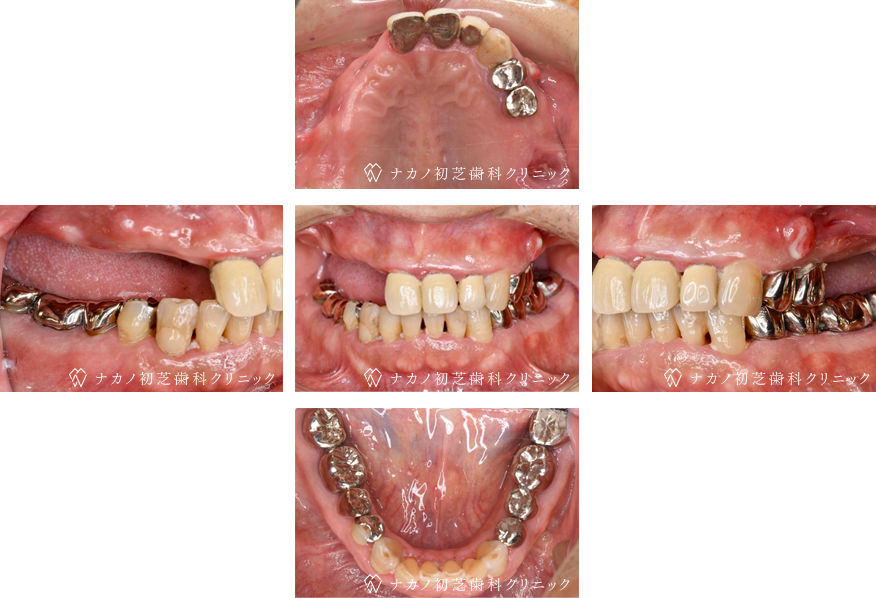

インプラント・13本 (60代女性)

BEFORE

AFTER

年齢 60代女性

治療内容 インプラント治療13本(骨造成の併用)

インプラント治療とは、歯を抜いた所にチタン製の人工歯根を埋入し、その上に歯を入れる方法です。骨を増やすことで、より審美的に治療が出来ました。費用 1本 400,000円(税込 440,000円)

リスク・副作用

腫れ・疼痛・違和感を感じるなどの症状を生じることがあります。